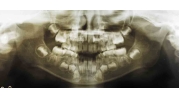

| 初診時